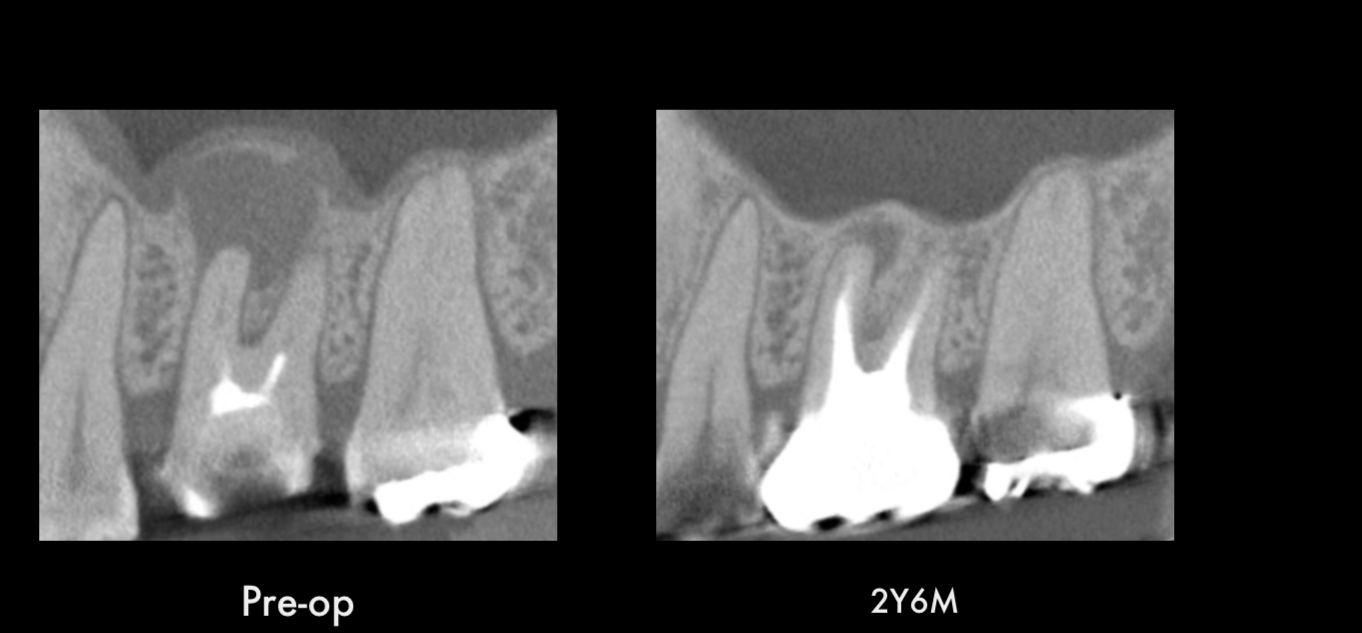

* 診断: まずはレントゲン撮影や視診などを行い、歯の状態を詳しく調べます。虫歯の進行度合い、根管の数や形状、根尖病巣の有無などを確認し、治療計画を立てます。

* 根管充填: 洗浄・消毒した根管に薬剤を詰めます。根管の内部を隙間なく充填することで、細菌の侵入を防ぎ、再感染のリスクを低減します。